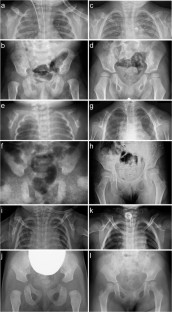

There have been several reports on heterozygous loss of function variants in PBX1 associated with congenital anomalies of the kidney and urinary tract (CAKUT). We report three patients harboring de novo heterozygous missense variants in PBX1, who did not have CAKUT, but instead presented with respiratory failure, developmental delay, and, the most important, a unique skeletal phenotype characterized by broad and short clavicles with coracoclavicular ankylosis and broad ischia with premature fusion of the ischiopubic synchondrosis. All the variants are clustered at the last portion of the homeobox domain. This phenotype is consistent with mouse models with functional dysregulation in Pbx1 or its interacting factor, Emx2. This study highlights a previously not reported phenotype affecting the clavicles and ischia due to PBX1 variants and expands the clinical spectrum of PBX1-related disorders.